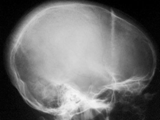

Sickle cell-skull

Sickle cell-skull